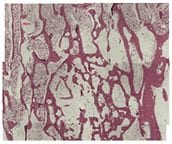

genex Implantation

36 Weeks

(Large animal model. Decalcified histology H&E stain)

genex restores bone to normal trabecular structure in 36 weeks1